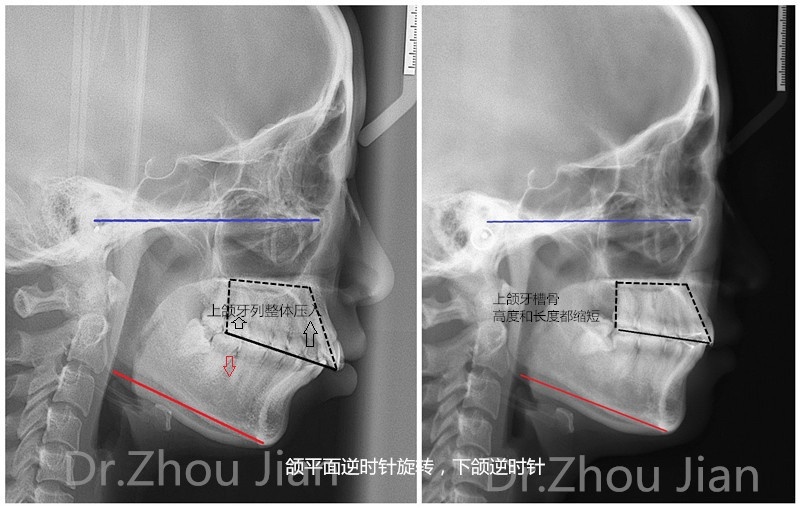

一下x光片,见证奇迹的时刻,下颌发生的逆时针旋转,让你的下巴"长"出来

下巴后缩ct侧面照